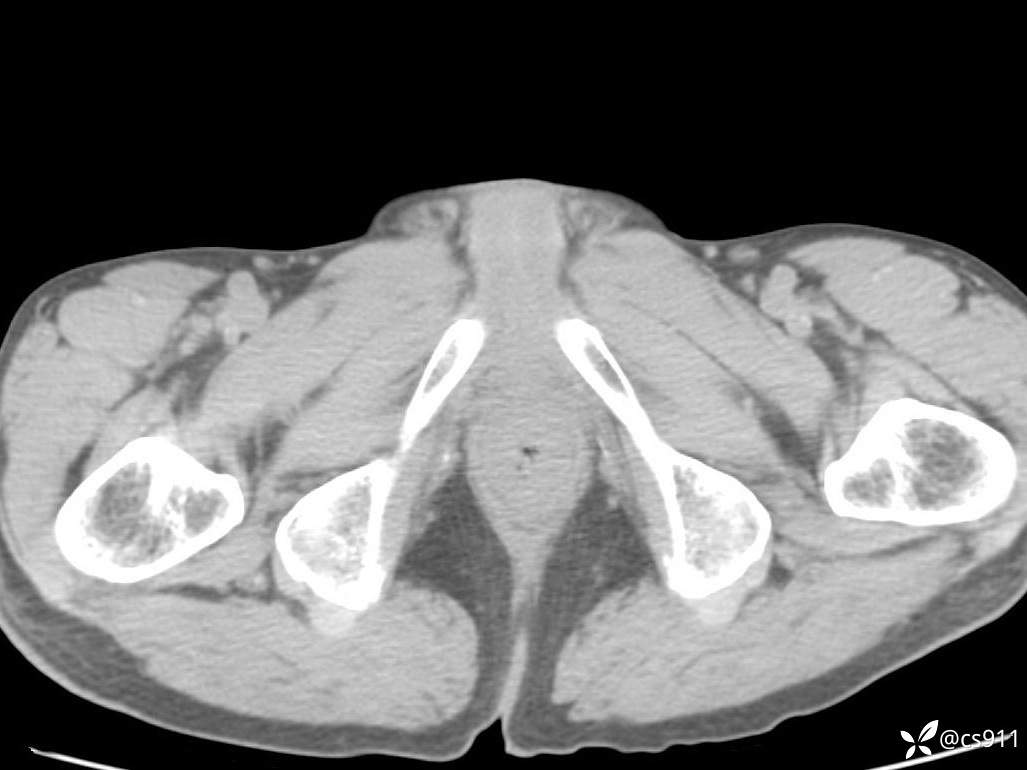

男,77岁,腹痛、腹胀伴恶心呕吐1天。呕吐胃内容物,非喷射性呕吐,有咖啡色样胃内容物,诉有胃穿孔病史。查体:全腹平,下腹部压痛,全腹无反跳痛,叩诊呈浊音,移动性浊音阴性,肠鸣音减弱,1-2次/分。肛检:直肠未扪及明显肿物,可触及大量粪块。